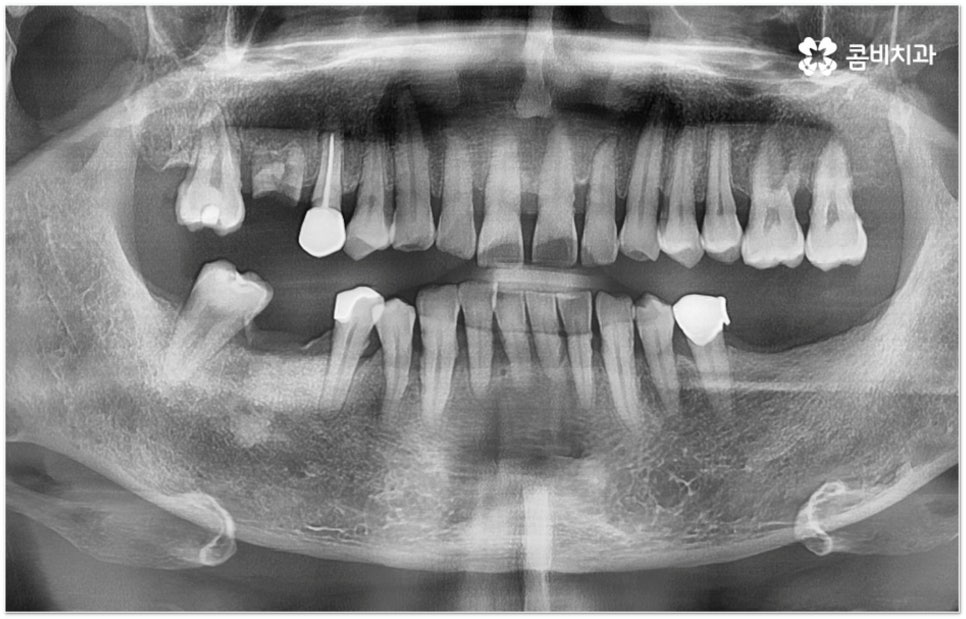

그러나 임플란트는 잇몸뼈에 직접 심어서 고정시키는 방식인 만큼 만약 환자분의 잇몸뼈가 부족하거나 치아가 빠진 후 오랜 시간이 지나 이미 잇몸뼈 소실이 상당 부분 이루어진 상태라고 한다면 먼저 골이식을 통해 이를 보충한 후 식립을 진행하는 뼈이식임플란트 방식을 이용할 필요가 있어요. 골이식 과정은 바탕이 되는 잇몸뼈의 밀도나 높이, 두께가 부족한 부분에 이식 재료를 심어주어 뼈를 재건해 주는 것인데 충분한 시간을 두고 무리하지 않게 진행하는 것이 뼈이식임플란트 수술의 성공률 및 안정적인 지속성을 높일 수 있는 방법이 될 거예요.

뼈이식임플란트 가 필요한지 살펴볼 때 3D CT 촬영과 같은 정밀 진단을 통해서 환자분의 잇몸뼈 두께 등 치조골 상태 뿐 만 아니라 구강 구조, 치아 및 잇몸 상태, 신경관 위치, 상악동까지의 거리 등을 꼼꼼하게 확인하여 치료 계획을 세우고 필요하다면 구강 질환에 대한 치료나 상악동 거상술 등을 선행하며 잇몸뼈 부족에 대해서도 골이식 과정을 먼저 진행하게 되는데요, 이러한 뼈이식임플란트 시술은 상당히 고난도의 복잡한 치과 진료인 만큼 관련 임상 경험이 풍부한 의료진과 함께 하는 것이 굉장히 중요하며 또한 수술 후 관리 면에서도 더욱 신경을 써 주시길 당부드리고 있어요.